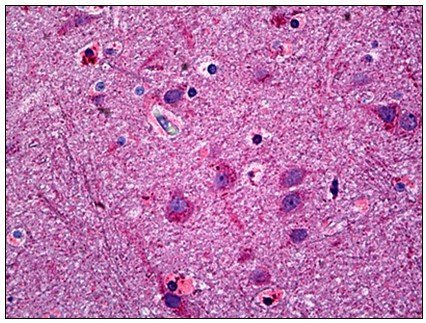

Supportive validation

- Submitted by

- antibodies-online (provider)

- Main image

- Experimental details

- Human Brain, Cortex: Formalin-Fixed, Paraffin-Embedded (FFPE)